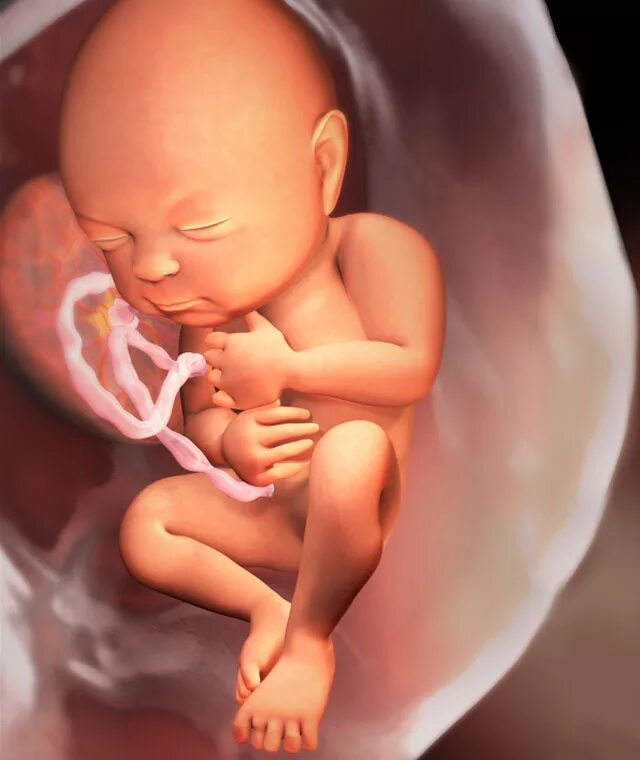

Как выглядит ребенок в 34 недели